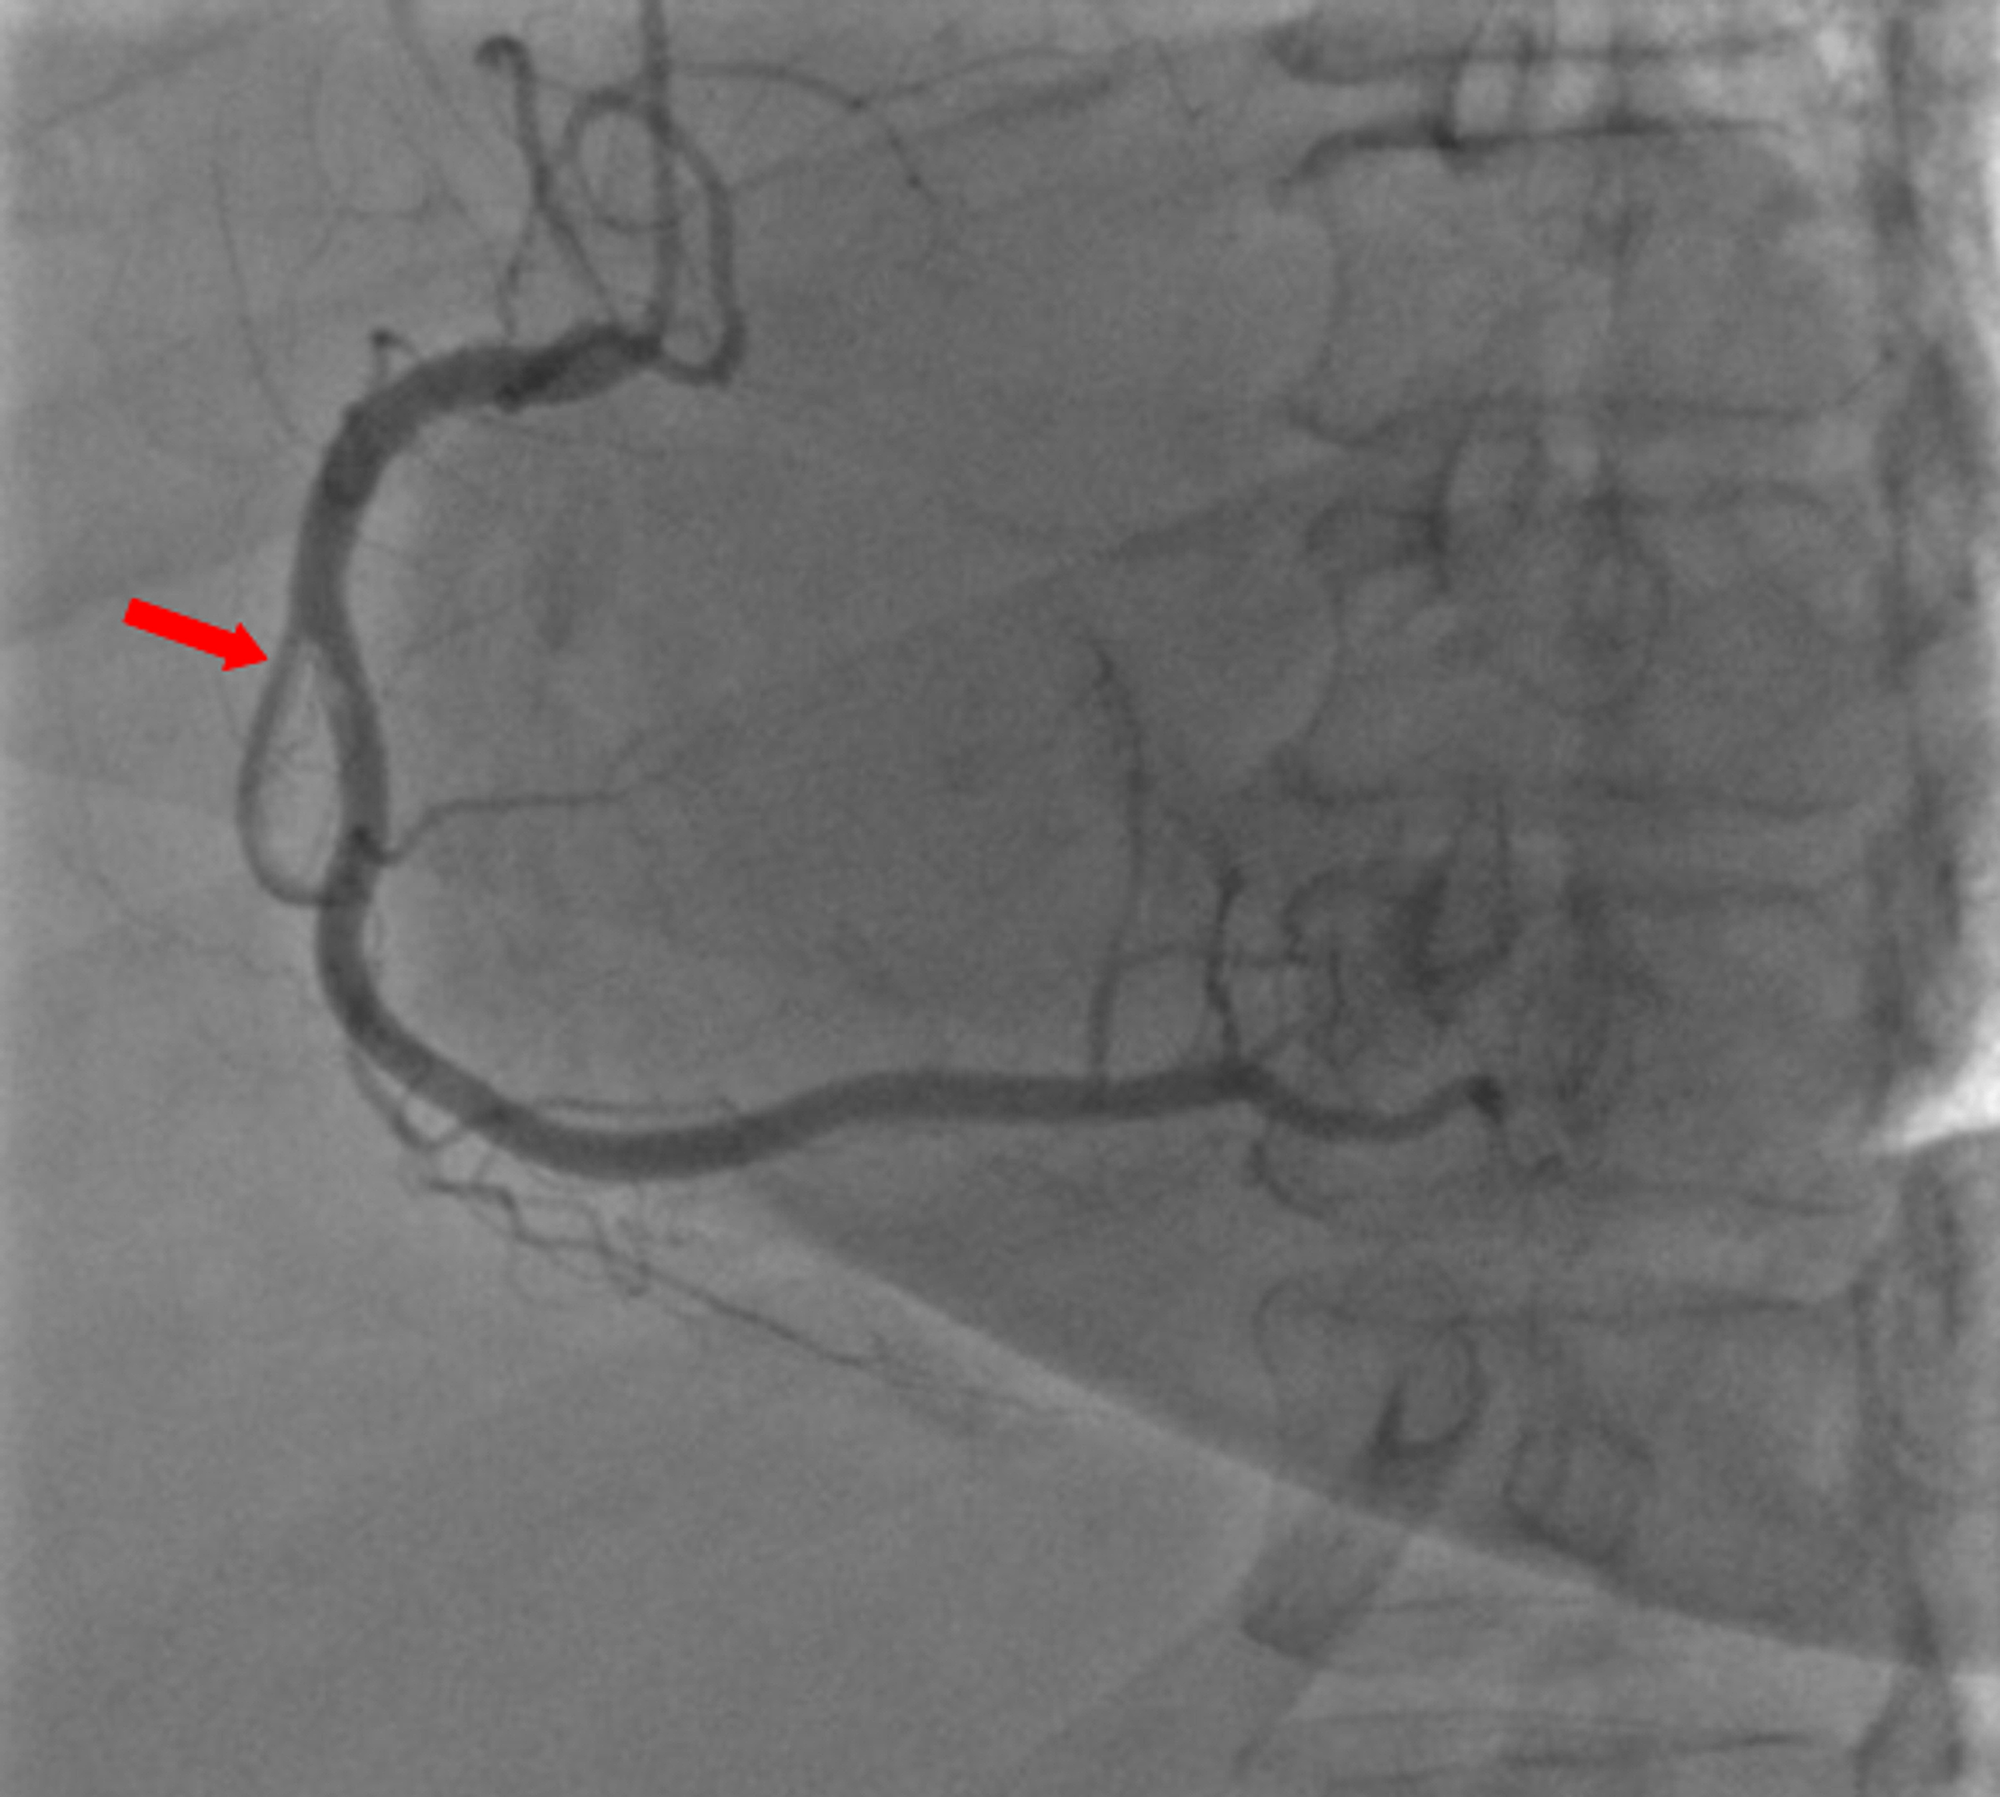

A 59-year-old woman was admitted to the emergency department with sudden onset of chest pain for five hours. She had hypertension (treated with β-blockers) as a cardiovascular risk factor. She was diagnosed with advanced non-small-cell lung cancer with liver metastases one month previously. The patient was not considered for surgical resection, she was scheduled for chemotherapy, and, consequently, no antineoplastic treatment had been initiated yet. Prophylactic anticoagulation was not indicated On clinical examination, her blood pressure was 150/90 mmHg with a pulse of 100 beats per minute, oxygen saturation of 95%, and normal heart sounds. The 12-lead electrocardiogram showed sinus rhythm with a heart rate of 102 beats for minutes and ST-segment elevation in all leads except aVR where ST-segment depression was noted (Figure 1). Her laboratory test results revealed a baseline troponin T level of 1212 ng/ml (normal range < 26 ng/ml). Also, the echocardiography findings revealed akinetic walls from the mid to apical septum and anterior and inferior walls. The ejection fraction was estimated to be 39%. Therapy was started with clopidogrel, aspirin, and low-molecular-weight heparin. The patient underwent a coronary angiogram from the right radial approach, which revealed the presence of an extended thrombus in the left anterior descending artery (LAD), and another thrombus was found in the second segment of the right coronary artery (RCA) with thrombolysis in myocardial ischemia (TIMI) III flow and without any atherosclerotic lesions in the coronary artery tree (Figure 2 and Figure 3), therefore, balloon angioplasty and/or stent placement was not considered. The patient was taken to the coronary care unit (CCU) and tirofiban infusion was administered for a period of 48 hours. In view of persistent breathlessness, pulmonary embolism was suspected. There were no symptoms or clinical signs suggestive of deep venous thrombosis. A computed tomographic pulmonary angiography was performed and showed a distal pulmonary embolism (Figure 4). The patient was discharged on acenocoumarol to be followed as an outpatient. At her 45 days follow-up, she did not report any episode of chest pain, bleeding, as well as any thrombotic events.